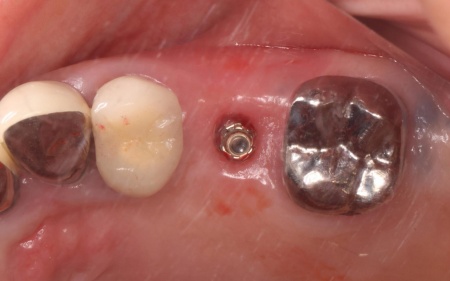

3ヶ月後、顎の骨の状態が良好であることを確認し、インプラントを埋入する手術を実施しました。

後日、インプラントが顎の骨にしっかりと結合したため、被せ物を作製します。

完成した被せ物を装着し、噛み合わせや使用感に問題がないことを確認して治療を終了しています。